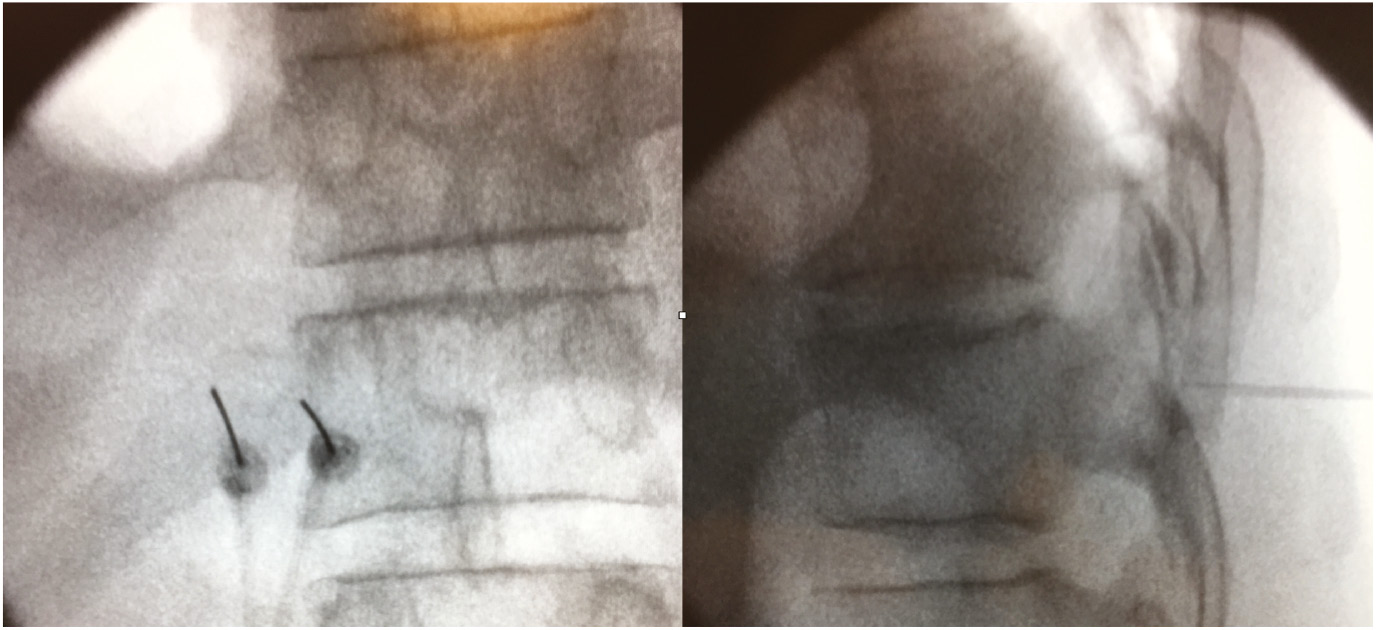

For bipolar RF neurotomy of thoracic medial branch, two 22 gauge 10 cm, sharp and straight RF insulated cannulas with an active tip of 10 mm, two 10 cm CSK-TC10 electrodes and a Cosman G4 RF generator (Cosman Medical, Inc., Burlington, MA, USA) were used. The procedure was performed with the patient in prone position on a radiolucent table. The C-arm of the fluoroscope was positioned in the axial plane and the proper level was identified by a radiopaque marker. The C-arm was turned cephalocaudal in order to square the end plates of the vertebrae. After identifying the transverse process, the skin was anesthetized with 0.5–1.0 mL of 1% lidocaine superficially and a RF cannula was inserted at the superior and lateral most portion of the transverse process. It was advanced in a tunnel view method until bone contact with the transverse process was made. A second similar RF cannula was inserted 5–10 mm medial and inferior to the first RF cannula in a similar manner as the first cannula until bone contact was made at the angle of the transverse and superior articular processes. A lateral fluoroscopic view was done to ensure that the tips of both cannulas were posterior to the line that connected the posterior aspects of the intervertebral foramina. Satisfactory final placement for both cannulas was confirmed with anteroposterior and lateral fluoroscopic views (Fig. 1). Neurostimulation was carried out first with 50 Hz which reproduced the pain, then followed with 2 Hz. The 2 Hz motor stimulation elicited contraction of the multifidus muscles at intensities below 0.5 V [3]. Subsequently, 0.5 mL levobupivacaine 0.5% was injected through both RF cannulas. Two RF electrodes were then inserted through the two cannulas, and the electrode tip temperatures were raised to 80°C for 90 s. One bipolar RF lesion was made for the medial branch of each thoracic ramus. As for treatment of facet joint pain involving two regions, e.g. cervico-thoracic and thoraco-lumbar regions, RF neurotomy of cervical and lumbar medial branches were carried out based on the conventional monopolar technique previously described [18, 19]. Patients were discharged home with oral celecoxib 400 mg daily, pantoprazole 40 mg daily and paracetamol 1 g 3 times daily for 5 days to relieve post-procedural needle soreness.

Anteroposterior and lateral fluoroscopic images of bipolar RF cannulas at target points (transverse process of thoracic vertebra). Note the cannulas are parallel and 10 mm apart to each other within the area of the transverse process in anteroposterior view. In lateral view, the tips of both the cannulas are located posterior to the line that connects the posterior aspects of the intervertebral foramina.